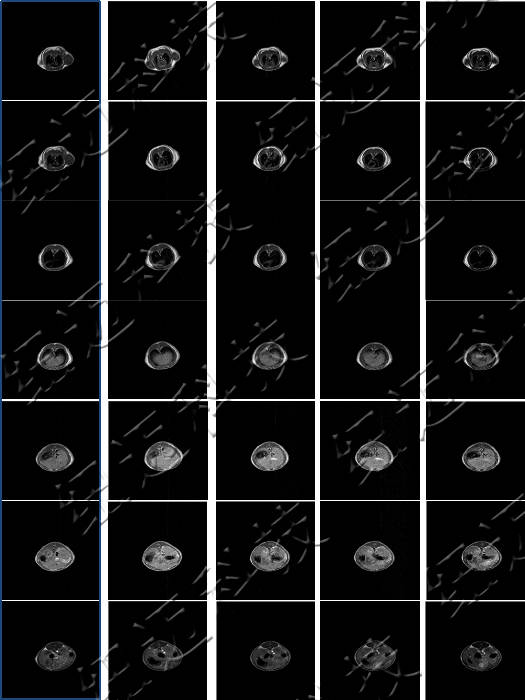

蛋白模拟仿生合成Gd:CuS造影剂用于体内肿瘤成像研究

核磁共振测造影剂弛豫率及造影剂成像

测试钆类MRI造影剂弛豫率测试以及造影剂样品的T1加权成像。

核磁共振成像(MRI)目前普遍应用于医学检测成像中,具有无辐射损伤的安全性,可任意方位断层扫描等技术灵活性,加以涵盖质子密度、弛豫、加权成像以及多参数特征的优势,已成为当代临床诊断中最有力的检测手段之一,然而临床发现某些不同组织或肿瘤组织的弛豫时间相互重叠,导致诊断困难。

核磁共振成像因其具有无创、快速、高解析率、高对比度等特点,在临床上广为使用。特别是在肿瘤的诊断中,该技术利用病变组织和正常组织物理特性的不同而获得的结构、功能影像,已经成为原发肿瘤和肿瘤转移早期诊断中不可或缺的重要依据。